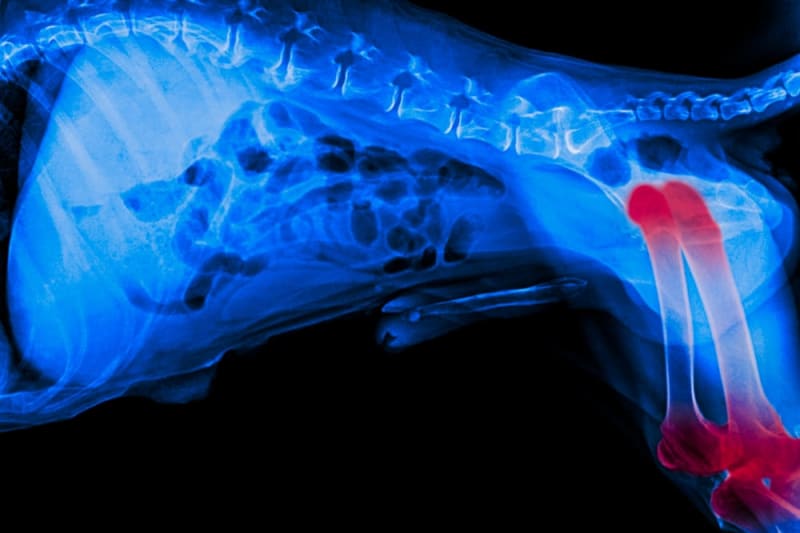

from cardiffcaninekneeclinic.co.uk

Patellar Luxation Dog Knee Surgery Cardiff Cardiff Canine Knee Clinic